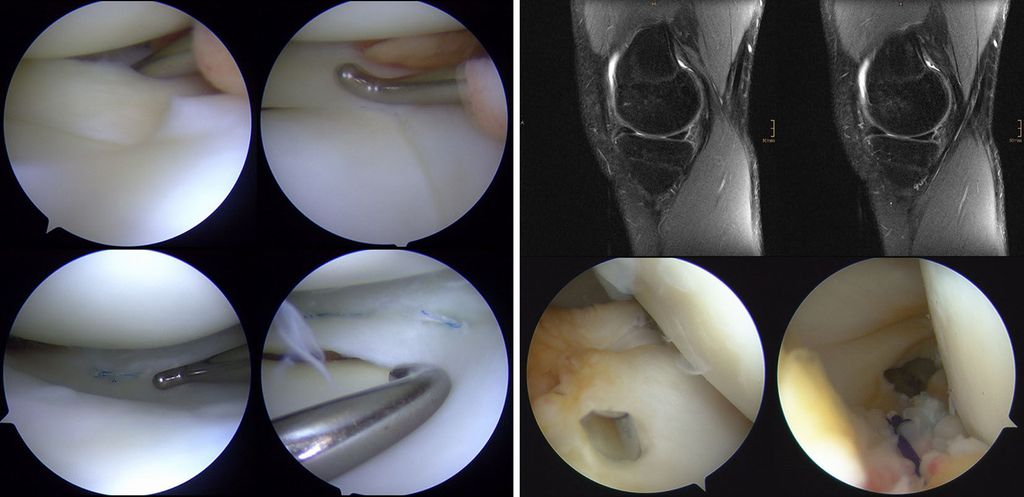

Bei der operativen Versorgung der McKeever-Verletzungen stellt die arthroskopische Versorgung heute den Goldstandard dar. Abhängig von der Fragmentgröße und -form stehen mehrere Fixationsmethoden zur Verfügung, die arthroskopisch, arthroskopisch assistiert oder auch offen durchgeführt werden können. Bei der arthroskopischen Reposition mit transossärer Auszugsnaht mit resorbierbarem Nahtmaterial ist ein Zweiteingriff zur Materialentfernung nicht erforderlich und die Schädigung der Wachstumsfuge ist minimal (Abb. 4).

Abb. 4: Schematische Darstellung und arthroskopische Bilder bei McKeever-Verletzung: Nach Reinigung des Frakturbetts und Reposition des Fragments erfolgt eine zweifache transossäre Auszugsnaht mit resorbierbarem Nahtmaterial (mod. nach Stotter und Reuter 2022)44

Es stehen unterschiedliche arthroskopische Nahttechniken zur Verfügung, die entsprechend der Rupturlokalisation und -form Anwendung finden (Abb. 5). Läsionen der medialen Meniskusrampe, die häufig mit Rupturen des VKB assoziiert sind, lassen sich durch direkte Visualisierung mittels Gillquist-Manöver darstellen und gegebenenfalls über ein zusätzliches posteromediales Portal versorgen (Abb. 5).39 Rupturen der posterioren Meniskuswurzel können zu einer Extrusion des Meniskus mit entsprechendem Funktionsverlust führen.40 Die Versorgung kann mit All-inside-Nahtsystemen oder transossären Auszugsnähten erfolgen. Bei instabilen Meniskusrissen in der Zone 3 (weiß-weiße Zone) können auch im Kindesalter Teilresektionen notwendig werden.

Abb. 5: Arthroskopische Bilder einer basisnahen Vertikalruptur am Außenmeniskushinterhorn bei einem 14-jährigen Patienten mit VKB-Ruptur, Refixation mit 2 All-inside-Nähten (links); MRT und arthroskopische Bilder einer medialen Rampenläsion, assoziiert mit einer VKB-Ruptur bei einem 16-jährigen Patienten, die Naht erfolgt über ein posteromediales Portal (aus Reuter und Stotter 2022)45